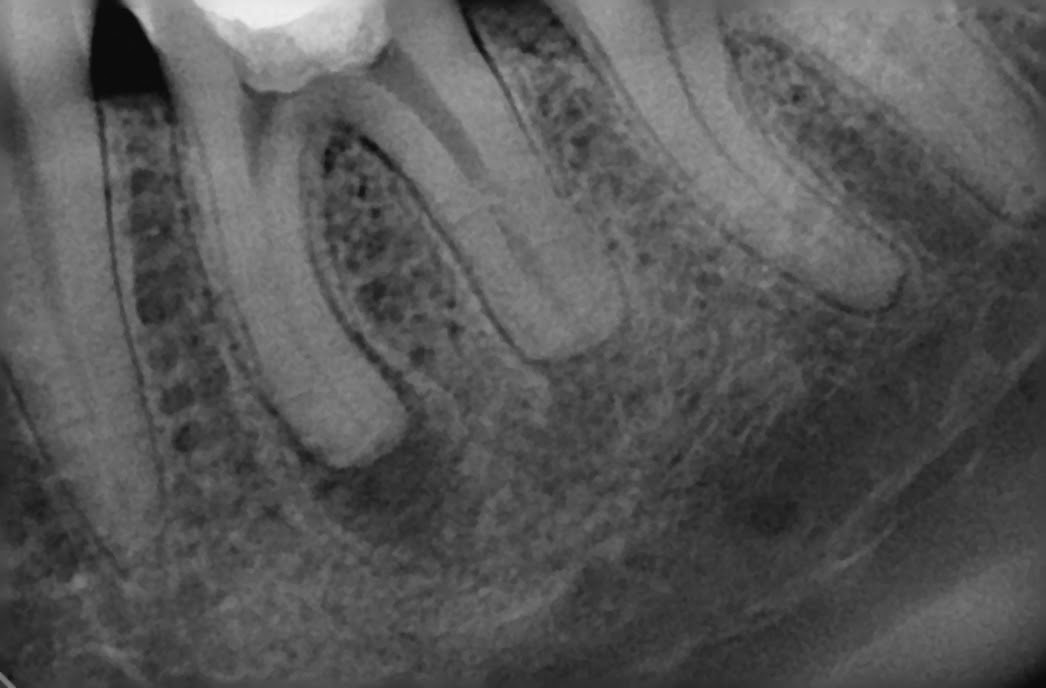

Mašinskom obradom kanala korjena uspjeli smo smanjiti procenat liječenih zuba koji se naknadno terapijski tretira oralno hirurškim zahvatom koji se zove apikotomija, odnosno mašinskom obradom kanala korjena zuba smanjili smo šanse da se zub nakon određenog vremena oralno hirurški zbrinjava. Prisutni su i slučajevi gdje je pacijenta iz druge ambulante kolega poslao da zub operiše tj. da mu se uradi apikotomija. Mi smo uspjeli takav zub konzervativno da zbrinemo bez hirurške intervencije zahvaljujući mašinskoj obradi kanal korjena (zadnje dvije slike u dnu)!!!